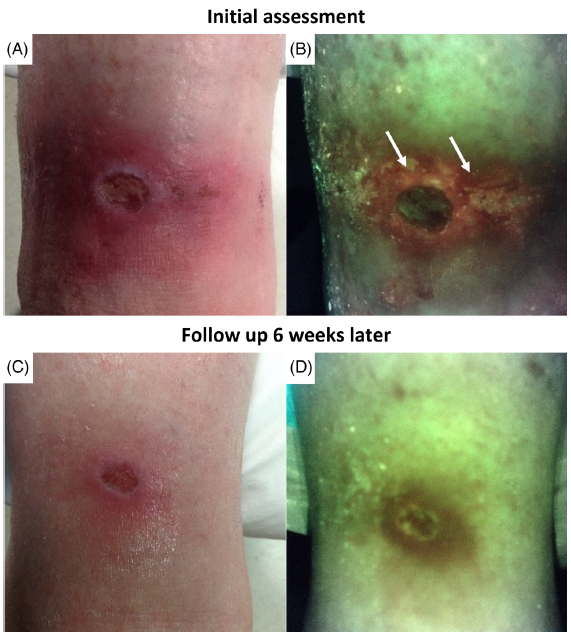

Diagnosis and treatment of the invasive extension of bacteria (cellulitis) from chronic wounds utilizing point-of-care fluorescence imaging

Andersen, A. et al. Int Wound J 2021